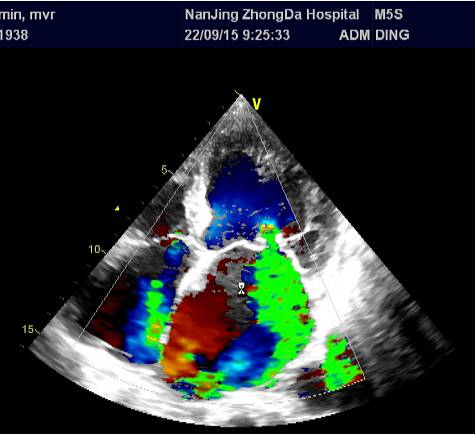

\u000b心超(2015-09-22):二尖瓣前叶脱垂伴中度关闭不全、主动脉瓣钙化,LA(5.4)、RA(4.2)、LV(6.4)、 LVEF 0.40,三尖瓣中度、主动脉瓣中度返流、肺动脉高压(PG=36mmHg)、心功能减低 。